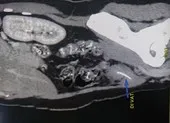

Qua hình ảnh chụp cắt lớp (cản quang) vi tính cột sống cổ, các bác sĩ hội chẩn và chẩn đoán bệnh nhân bị áp xe cổ lan trung thất, đái tháo đường type 2, có dị vật. Bệnh nhân được chỉ định phẫu thuật cấp cứu.